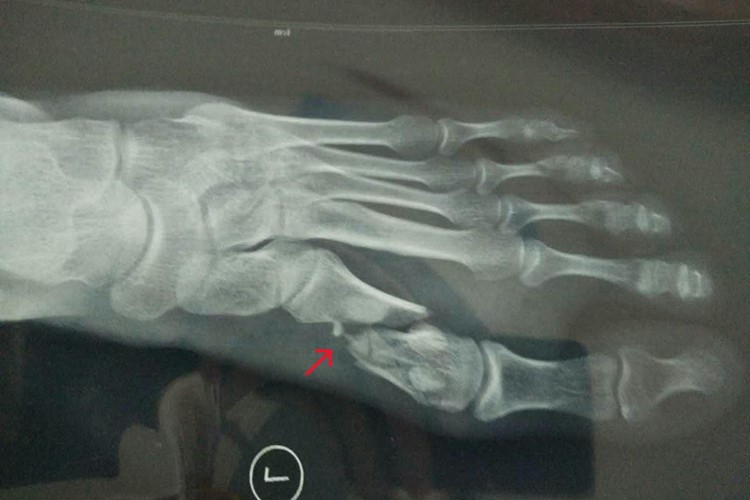

左足第一跖骨基底部骨折后,会引起局部皮肤肿胀、瘀斑,影像学检查可以看到明显骨折痕迹,多是由于外界暴力撞击引起。

左足第一跖骨基底部骨折后,局部常会表现为充血、发红、肿胀、瘀斑。骨折处压痛,纵向挤压痛明显,行走受限。通过影像学检查后,可以看到明显的错位、骨折处。